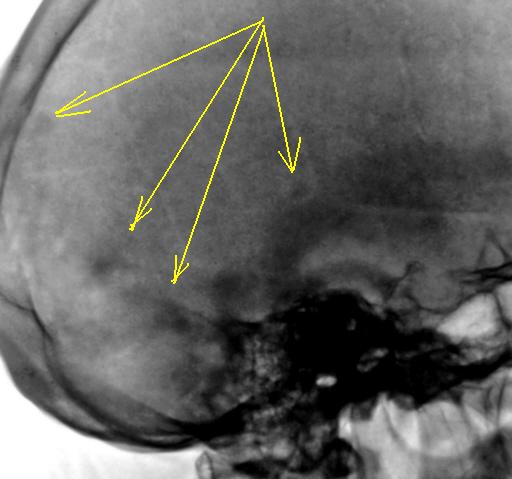

А, что "это" за уплотнения.

Уплотнения? Возможно эностозы.

Эностозы???

Может тогда только участки локального остеосклероза? Ведь..."Эностоз (enostosis; эн- + греч. osteon кость + -оз) — заращение костномозговой полости костной тканью"....

Да, наверно, правильно участки остеосклероза.